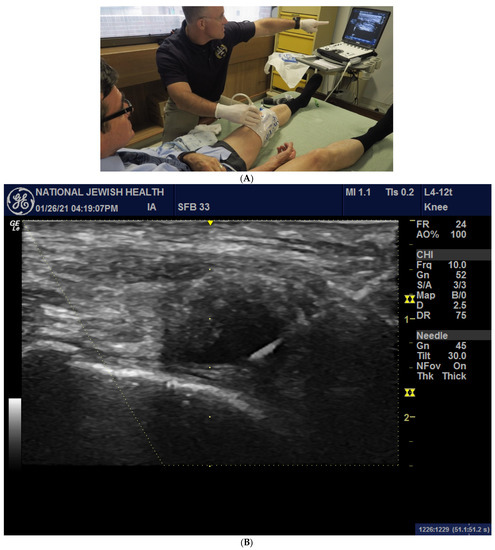

An external pneumatic compression device (KneeTapTM Arthroventions LLC, Denver, CO, USA) was inflated to 100 mmHg as previously described [24]. Ultrasound images were acquired using a GE LOGIQ e ultrasound (Fairfield, CT, USA) with a 12L-RS linear array probe, as displayed in Figure 1A,B.

Figure 1.

(A) An inflated pneumatic compression device with an image displayed on an ultrasound screen prior to successful knee aspiration of synovial fluid. Image courtesy of Dr. R. Meehan and Dr. R. Scheuring. (B) US image of a study subject during needle insertion, displaying a bright 20-gauge needle entering from the upper right-hand corner of the image with the tip placed within the intra-synovial space (dark anechoic region) during inflation and prior to injecting IA HA product.